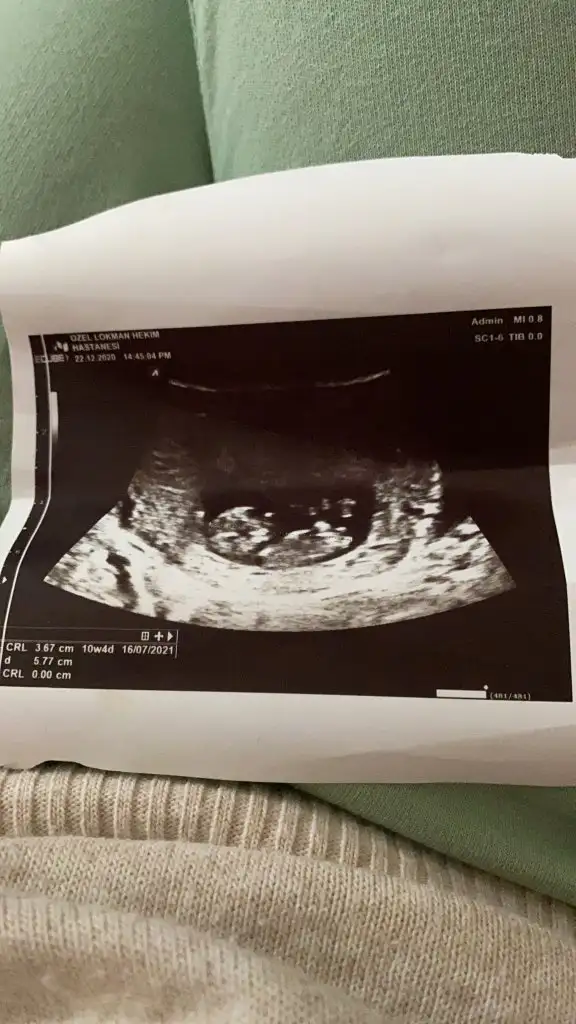

Kaç haftalıkKızlar tahmin yaparmısınız cinsiyet

Burda 10hafta 4 günlüktüKaç haftalık

Tahmin için yetersiz canım 11-12-13 olmalı yine de ikra meyraya at istersenBurda 10hafta 4 günlüktü